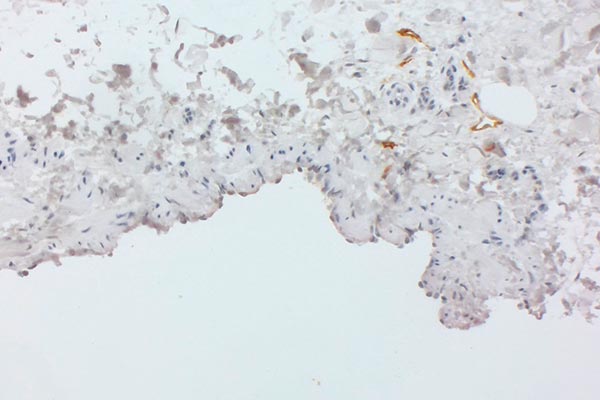

Immunhistologische CD31-Färbung, Gefäßendothelzellen färben sich damit spezifisch an, links 40-fache Übersicht, rechter Bildausschnitt 200-fache Vergrößerung. Die dysplastischen Räume sind mit CD31-positiven Endothelien ausgekleidet, dieser Marker bekräftigt damit den Gefäßcharakter der Läsion. Die Braunfärbung mit dem CD31-Antikörper entsteht membranständig an den auskleidenden Endothelzellen (Darstellung ähnlich einer zytoplasmatischen Färbung), wie dies in der Ausschnittsvergrößerung (rechts) zu sehen ist.

Die histopathologische Aufarbeitung zeigte dann auch den typischen Befund einer benignen Gefäßläsion (CD31-positiv) mit dysplastischem, asymmetrisch unregelmäßigem Wandaufbau. Wie für solche Slow-flow-Gefäßmalformationen typisch, ist die glattmuskuläre Gefäßwand nicht überall gleich dick und symmetrisch ausgebildet, sondern fehlt zum Teil sogar ganz (SMA, EvG). Kaum Proliferation des beteiligten Gewebes (Ki67 sehr niedrig). Die fehlende WT1-Positivität der betroffenen Gefäßendothelien ist ein weiterer Hinweis auf eine Gefäßmalformation. Wesentlichstes histopathologisches Unterscheidungsmerkmal zwischen einer lymphatischen Malformation und einer venösen Malformation ist die immunhistochemische Anfärbung des Podoplanin der Gefäßendothelien der Läsion mittels des Antikörpers D2-40. Nur die Gefäßendothelzellen einer lymphatischen Malformation (D2-40 positiv) färben hier an. In dem Präparat zeigten sich zusätzlich auch multiple dysplastische Gefäßmalformationsareale, deren Gefäßendothel nicht mit D2-40 anfärbte, also handelte es sich hierbei um Anteile einer venösen Malformation. Die korrekte histopathologische Diagnose ist daher auch eine kombinierte venolymphatische Malformation. Die klinisch und in der Bildgebung klar im Vordergrund stehende lymphatische Komponente steht in dem Präparat der hier gewonnenen Stanzbiopsie aus der Läsion gegenüber der venösen Komponente eher im Hintergrund.